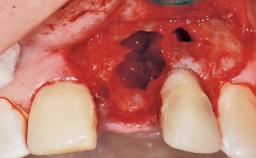

Late Flapless Placement of an Implant in a Maxillary Left Central Incisor Site

A 39-year-old male patient presented with a chief complaint of discomfort and gingival discoloration around his maxillary left central incisor. He was in good general health and was a non-smoker. His past dental history was significant because of the traumatic fracture of tooth 21 in a sporting accident at age 13. Initial dental treatment included endodontic therapy and a full-coverage restoration. The patient became symptomatic 5 years later, when structural failure of the tooth resulted in the dislodgment of the crown. Endodontic retreatment, apical surgery, and post-and-core restoration were performed.